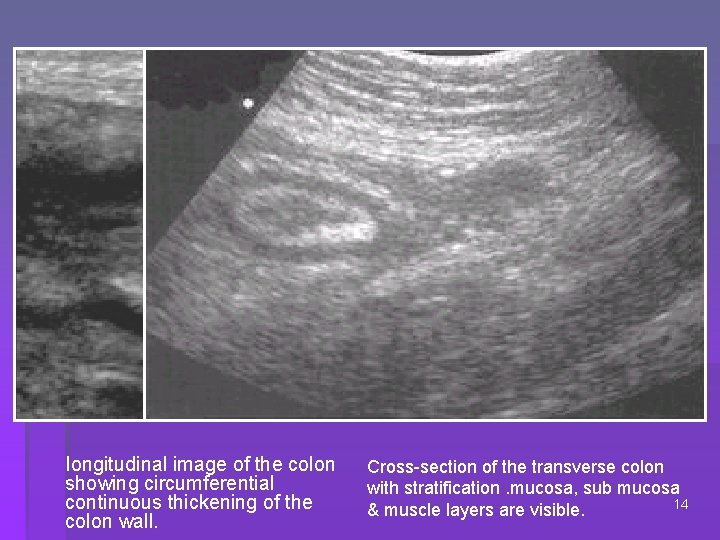

USG FINDINGS: CT FINDINGS: Moderately thick, hypoechoic wall Typical wall stratification maintained Loss of haustration Absent peristaltic motion Mural thickening < 1. 5 cm Target appearance of wall – submucosal edema( acute) Target appearance of wall – submucosal fat ( chronic) Increased perirectal and presacral fat 13

longitudinal image of the colon showing circumferential continuous thickening of the colon wall. Cross-section of the transverse colon with stratification. mucosa, sub mucosa 14 & muscle layers are visible.